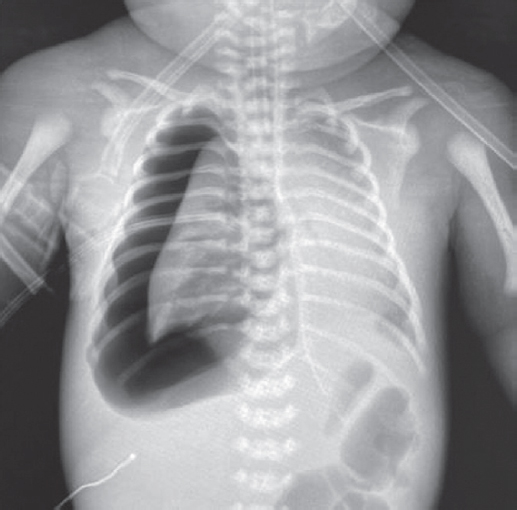

Состояние ребенка с рождения средней степени тяжести, обусловленное явлениями респираторного дистресса (умеренное втяжение межреберий, стонущее дыхание, тахипноэ до 60 в минуту), что потребовало проведения неинвазивной искусственной вентиляции легких (ИВЛ, nСРАР — nasal continuous positive airway pressure) c первых минут жизни [2]. На рентгенограмме отмечаются признаки транзиторного тахипноэ новорожденного (рис. 1).

Рис. 1. Рентгенограмма органов грудной клетки новорожденного с клиническими признаками респираторного дистресс-синдрома через 2 ч после рождения

Fig. 1. Chest X-ray of newborn with clinical signs of respiratory distress 2 hours after birth